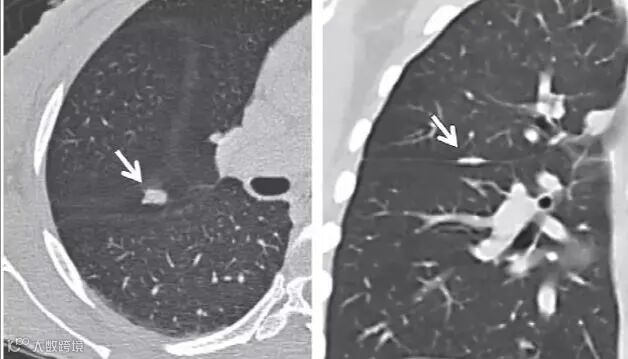

上图所示为边缘光滑、内含脂肪和钙化的实行结节,考虑错构瘤,不建议CT随访。

上图为中心钙化的实行结节,不建议CT随访。

上图左为斑片状结节影,右为重建后线样瘢痕或淋巴组织,不建议CT随访。